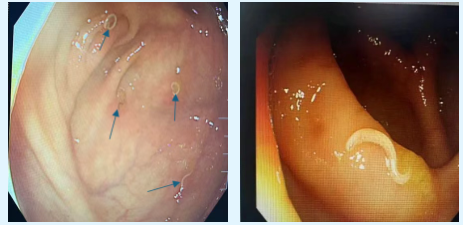

寄生虫悄然入侵

饮食卫生是关键

近期两例腹痛患者在结肠镜检查中意外发现肠道蛲虫,经驱虫药物治疗后康复。消化道寄生虫病多与食用被污染食物、水源或接触感染者有关,可能出现腹痛、腹泻、肛周瘙痒、贫血、营养不良等症状,可结合大便检查、血常规、胃肠检查确诊。

医生:注意饮食卫生、彻底清洗果蔬、煮熟肉类是预防关键!